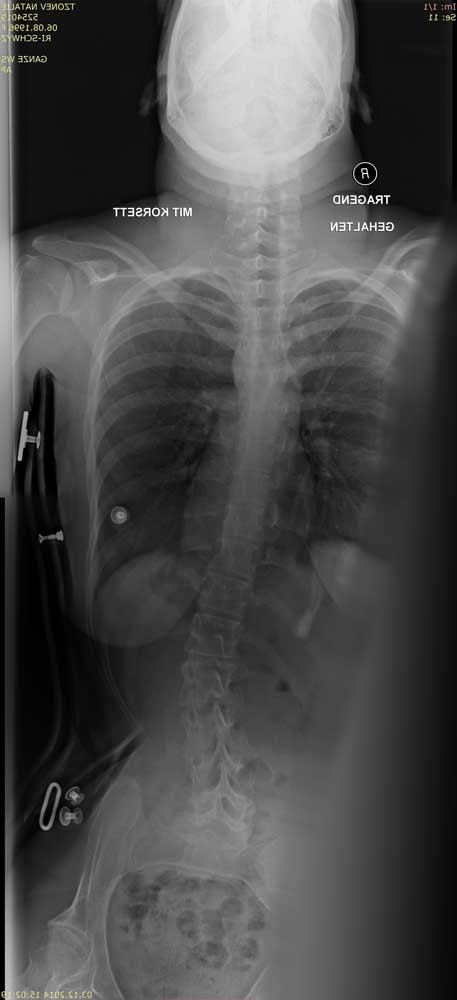

Standardisierte anterior-posteriore (a.-p.) Röntgenbilder wurden retrospektiv ausgewertet. Die Aufnahmen wurden bei allen Patienten in sitzender Position durchgeführt. Bei 3 Patienten wurden Röntgenbilder in stehender Position angefertigt. In liegender Position angefertigte Röntgenbilder waren nicht zulässig, da das maximale Ausmaß der Verkrümmung in dieser Position durch die fehlende Schwerkraft nicht sichtbar ist. Anhand der a.-p. Röntgenbilder wurden der Apex sowie die lumbalen und thorakalen Cobb-Winkel berechnet. Alle Winkel wurden mittels „Centricity Dicom Viewer V3.1“ gemessen. Bei demselben Krankenhaustermin wurden zwei Röntgenbilder angefertigt: eine erste Röntgenaufnahme (T1) mit Doppelschalenkorsett und nach 5 Minuten (T0) ein zweites Röntgenbild ohne Korsett. Dies war allerdings nur bei Patienten mit korrekter Anpassung des Doppelschalenkorsetts möglich. Bei den anderen Patienten betrug die Zeitspanne zwischen T1 und T0 nicht mehr als 3 Monate aufgrund notwendiger Anpassungen des Doppelschalenkorsetts durch den Orthopädietechniker. Der Grad der Korrektur des Cobb-Winkels im Bereich der Lenden- und Brustwirbelsäule wurde in Prozent des Messergebnisses ohne Korsett bei T0 ausgedrückt (Abb. 1 u. 2).

Die Abbildungen 3 und 4 zeigen die klinischen und radiologischen Befunde für eine 18-jährige Frau (Fall 17). In Abbildung 3 sind die klinischen Fotos ohne und mit Doppelschalenkorsett zu sehen. Abbildung 4 zeigt die Röntgenbilder dieser Patientin ohne (a) und mit (b) Doppelschalenkorsett.